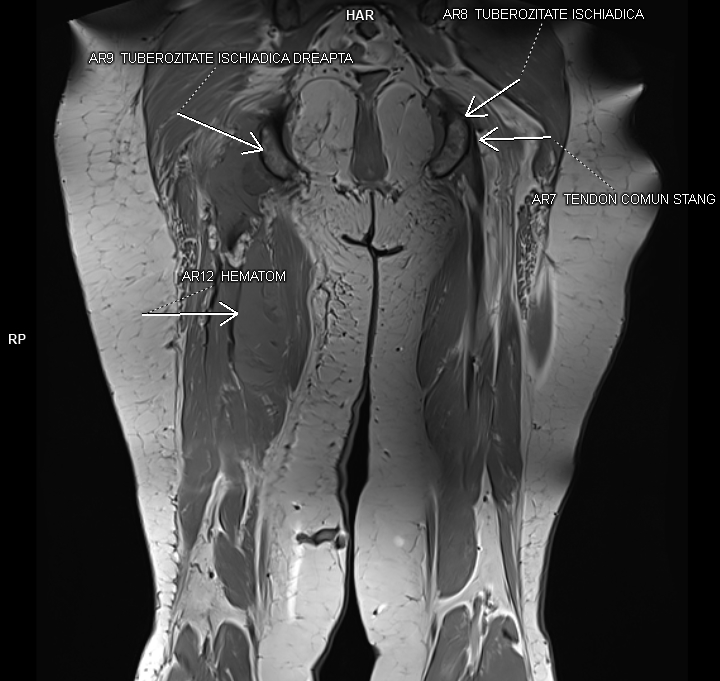

Figurile 1 si 2: coronal T1 coapsă bilateral

Figurile 3 si 4: coronal T2 cu saturația grăsimii coapsă bilateral

Discuţie caz nr 92: Harmstring lesion este dificil de tradus în limba română și se referă la leziunea celor trei mușchi ce se inseră pe tuberozitatea ischiadică: semitendinos, semimebranos și biceps femural. Cazul prezentat este a unui pacient care s-a aplecat la cumpărături să ridice o plasa și a simțit o durere puternică în spatele coapsei urmată de impotența funcțională si de creștere de volum a coapsei posterior. Pe imaginile postate se evidențiază avulsia tendonului comun al celor trei muschi ce se regăsește retractat inferior cu formarea unui hematom în vecinătate.